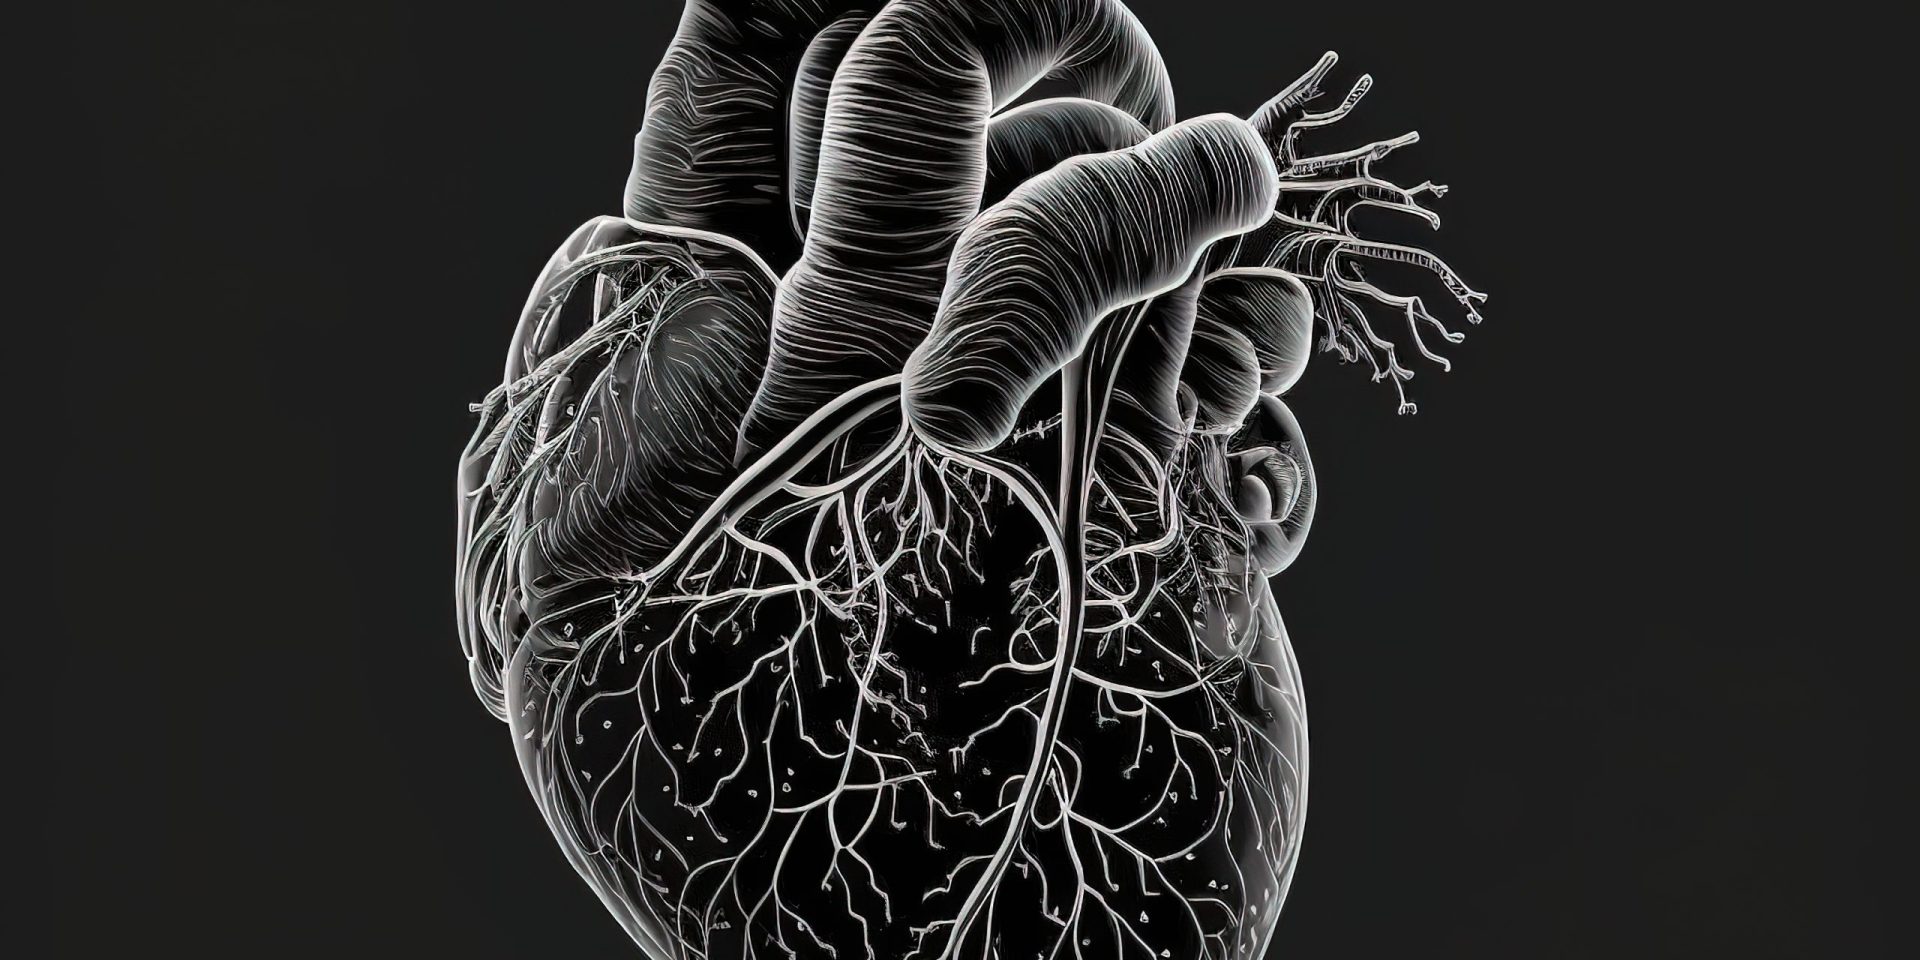

O efeito fisiológico agudo mais consistente do consumo de cannabis é a taquicardia dose-dependente (121,226,232). Embora isso geralmente não seja considerado perigoso para jovens usuários saudáveis, pode ser perigoso para aqueles que já sofrem de distúrbios cardíacos ou angina (118,921). A inalação do fumo de cannabis reduz a quantidade de exercício necessária para causar um ataque de angina em 50% (922) e tem sido associada a um risco cinco vezes maior de enfarte do miocárdio na primeira hora após fumar (232).

Isso pode ser causado por um aumento no débito cardíaco, demanda miocárdica de oxigênio, níveis de catecolaminas e carboxihemoglobina relacionados à Δ9-THC, bem como hipotensão postural (226,227,923).

Embora a taquicardia seja observada em usuários ocasionais e crônicos, a tolerância se desenvolve de forma relativamente rápida com o grau de taquicardia diminuindo com o uso. Após cerca de 8 a 10 dias de dosagem constante com 10 mg de Δ9-THC por dia (equivalente a 80 – 100 mg de cannabis contendo 10% de Δ9-THC), observou-se bradicardia (924) com diminuição da pressão arterial em supino (925 ).

Sabe-se também que a cannabis causa vasodilatação periférica, hipotensão postural e avermelhamento conjuntival característico após fumar (926).